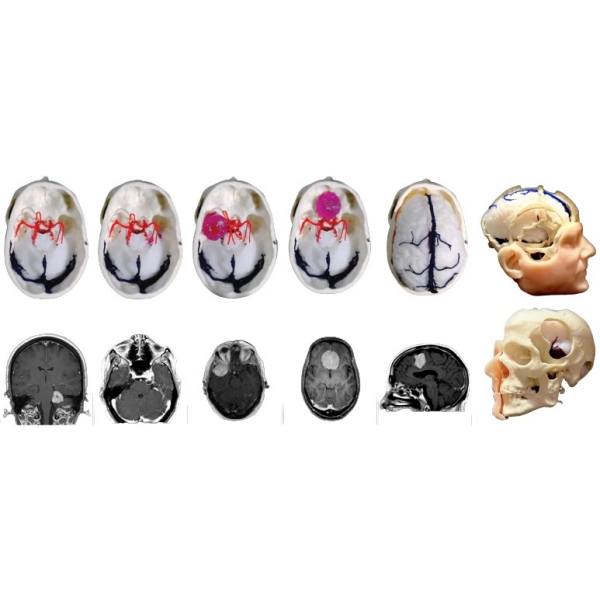

Človeška lobanja z vsemi kraniometričnimi točkami, razpokami in kanali. 1:1, pomanjšano na podlagi resničnega človeškega CT-posnetka na podlagi s podobnimi lastnostmi vrtanja kot človeška kost. Vključuje kožo, intrakranialno možgansko ovojnico, falx, tentorium, venske sinuse in vse lobanjske živce, arterije ter možgane, možganovino in možgansko deblo. Patologija: meningiom olfaktornega žleba, meningiom sfenoidnega krila, parafalcinalni meningiom, trigeminalni švanom in vestibularni švanom. Vse je bilo pridobljeno iz resničnih primerov, vključno s slikami DICOM za predoperativno načrtovanje.